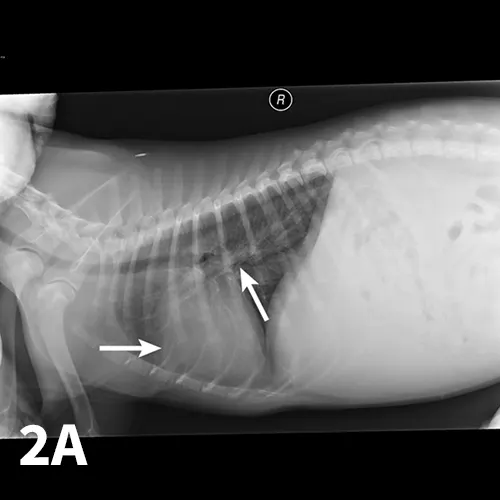

Lateral and VD thoracic radiographs of a dog with PHTN, showing mild right-sided enlargement of the heart and enlarged pulmonary arteries (arrows).

Thoracic radiographs are useful for evaluation but may underestimate the severity of the PHTN.

However, it may be possible to appreciate right-sided enlargement (reverse D) or pulmonary arterial enlargement (Figure 2).